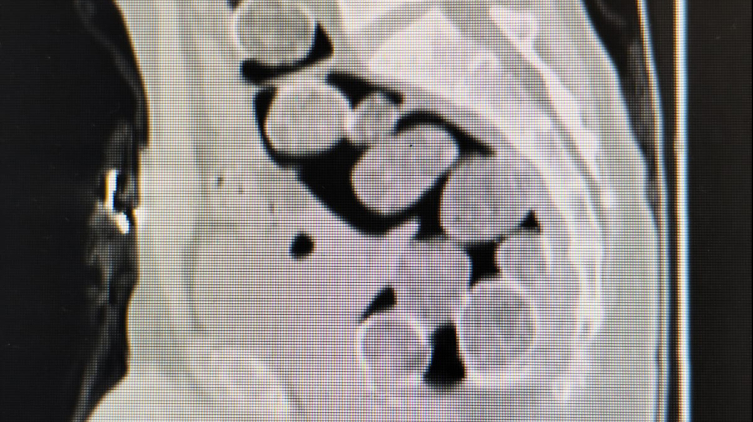

Zanlıların halsiz ve tedirgin davranışlarından şüphelenen polis, uyuşturucuyu yutmak suretiyle bağırsaklarında ve midelerinde getirebileceklerini değerlendirdi.

Samsun Eğitim ve Araştırma Hastanesi'ne götürülen şüphelilerin çekilen röntgen filminde, mide ve bağırsaklarında yabancı madde olduğu tespit edildi.

A.A. ve H.T'ye yapılan tıbbi müdahale sonucunda 18 paket halinde 500 gram sentetik uyuşturucu ele geçirildi.